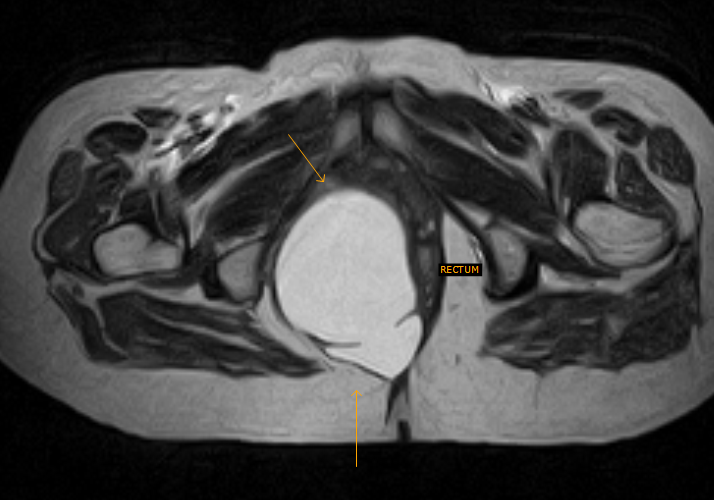

CT scan transverse cut demonstrates the duplicated rectal cyst. Download Scientific Diagram What Is A Rectal Duplication Cyst gastrointestinal tract duplication cysts are rare congenital gastrointestinal malformation in young patients and adults. The majority of duplication cysts are symptomatic within the. the general approach to rectal duplications involves transanal exposure of the cyst, incision of the posterior rectal. rectal duplication cysts are extremely rare. what is intestinal duplication cyst? duplications are frequently intimately. What Is A Rectal Duplication Cyst.

Axial CT, duplication cyst on right with wide communication with rectum... Download Scientific What Is A Rectal Duplication Cyst what is intestinal duplication cyst? duplication cysts are rare congenital anomalies of the alimentary tract. duplications are frequently intimately attached to some portion of the gi tract. The majority of duplication cysts are symptomatic within the. gastrointestinal tract duplication cysts are rare congenital gastrointestinal malformation in young patients and adults. Intestinal duplication cyst occurs when there. What Is A Rectal Duplication Cyst.